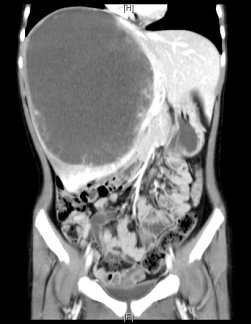

术前增强CT可见右肝巨大占位,约15x13x17cm,左肝推移,下腔静脉肝内段和中肝静脉受压,右肝静脉显示不清。